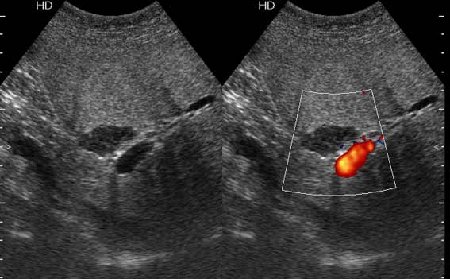

В печени выявлен гипоэхогенный очаг неокруглой формы, аваскулярный при цветовой доплерографии.

Простая и одновременно "сложная" задачка. По УЗИ; явный стеатоз печёночной паренхимы (теперь ключевые слова); на ФОНЕ СТЕАТОЗА определяется гипоэхогенное образование. Варианты? Очаговое образование; и менее вероятно участок гипостеатоза (но не похоже, есть чёткие границе, + не та локализация).

Вывод: надо иметь ввиду, что эхогенность это относительное понятие, эхогенность гемангиомы может изменятся при изменении положения обследуемого пациента (см. прикреплённую статью); не надо забывать что эхогенность образование это понятие относительное, т.е. относительно окружающей паренхимы печени! При стеатозе, гемангиома может выглядеть гипоэхогенно по отношению к гиперэхогенной паренхиме окружающей печени. И главное, есть сомнение-заказываем таргетное мультифазовое КТ.